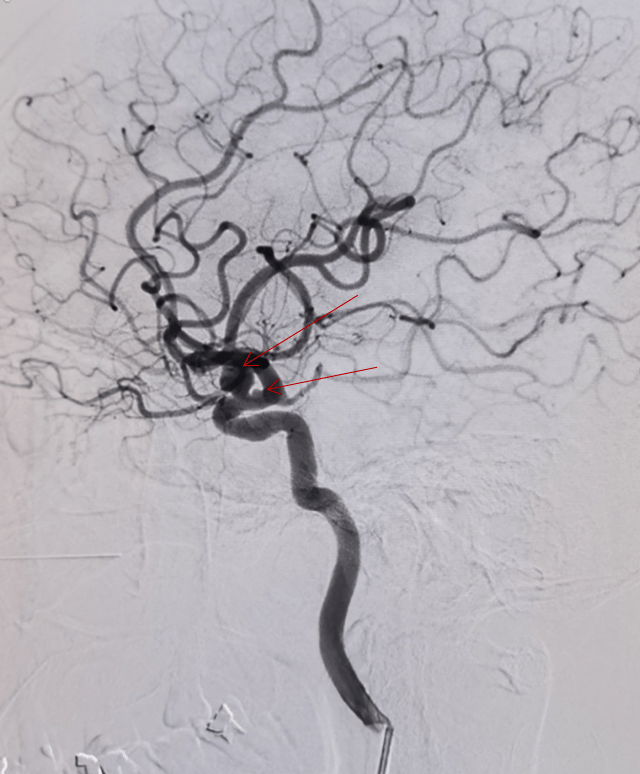

2019年3.8日齐鲁医院苏万东教授病例动脉瘤密网支架植入术tb5035